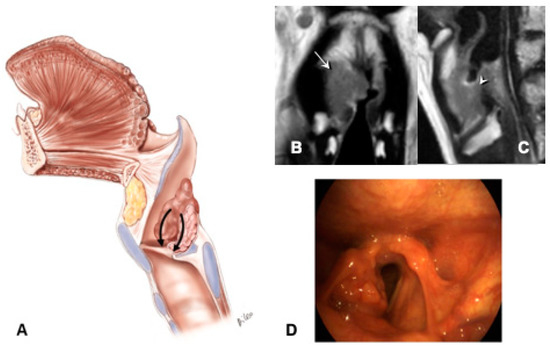

- Transglottic and infraglottic carcinoma with massive involvement of the CAU and of the posterior crico-arytenoid muscle, reaching the hypopharyngeal submucosa (Figure 5):

- The tumor massively infiltrates the SPGS and IPGS, the thyro-arytenoid space and/or posterior crico-thyroid space, it blocks the arytenoid laterally corresponding to the lateral crico-arytenoid muscle, extending downwards medially into the infraglottic site and puncturing the conus elasticus.

- Infraglottic extension >10 mm, evaluated exactly at the free edge of the TVC midline, with progression toward the posterior commissure.

- The tumor invades the arytenoid and, very often, the cricoid, involving the posterior crico-arytenoid and the interarytenoid musculature, reaching the hypopharyngeal submucosa.

- Possible involvement of the contralateral CAU.